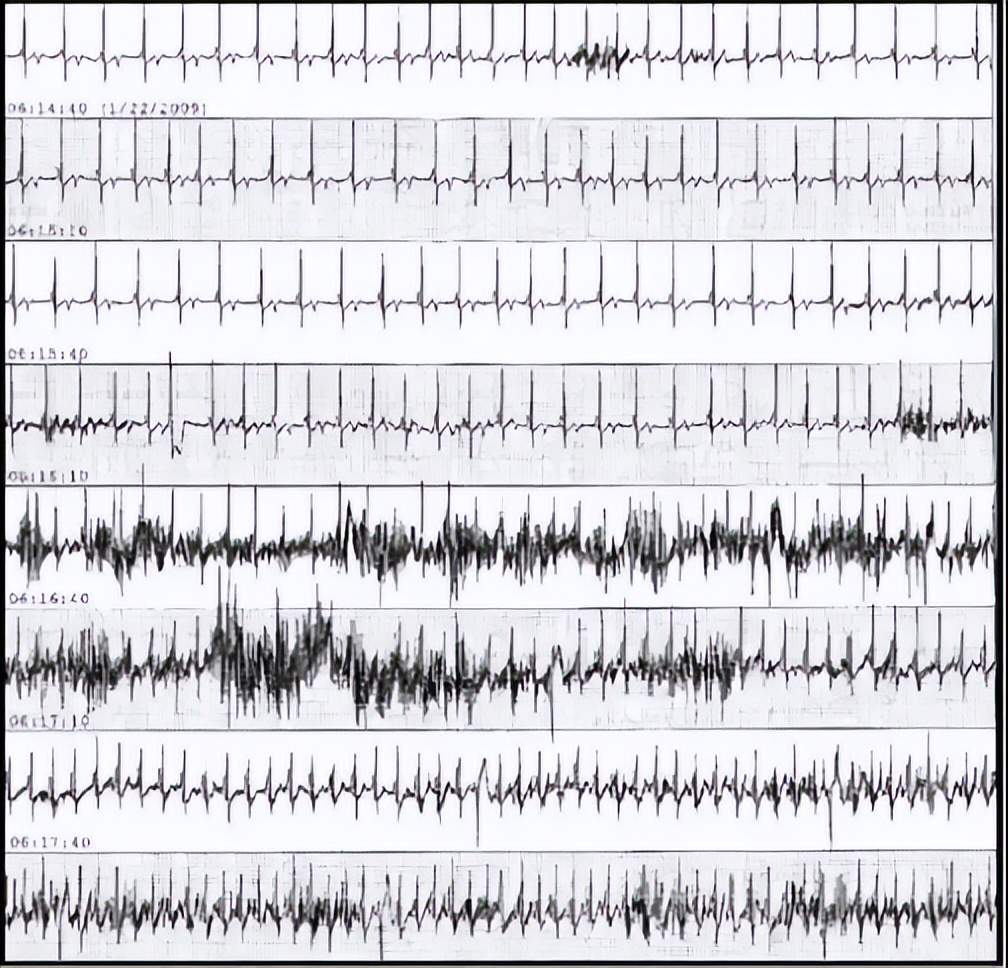

患者帕金森病右上肢规律震颤,Ⅰ、Ⅱ、aVR、aVL、aVF导联可记录到频率、波形规则的“室速波”,本图终末部似为“室速”蜕变为“室颤”,但仔细观察发现Ⅲ导联可记录到窦性P波,Ⅲ导联、V1-3导联可记录到正常的QRS波,“室速波”、“室颤波”实为右上肢规律震颤形成的干扰、伪差掩盖了正常的QRS波,右上肢震颤时肢体导联只有Ⅲ导联记录的心电波形和右上肢无关。

帕金森病右上肢规律震颤致假性室速、室颤12导联体表心电图

挠痒痒致假性室速、室颤心电监护记录